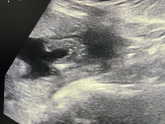

Второй скрининг❤️

17 февраля 2022 15:39

Вот и я дождалась второго скрининга. Слава богу малыш здоровый и крепкий. 390 грамм любви)) и наша девочка превратилась в мальчика))) растём дальше ❤️❤️❤️